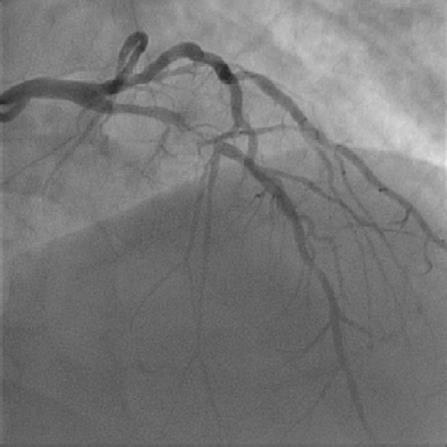

1477. Пациент в возрасте 57 лет подан в рентгеноперационную с острым инфарктом миокарда по передней стенке. данные коронарографии представлены на рисунке

какая оптимальная стратегия лечения?